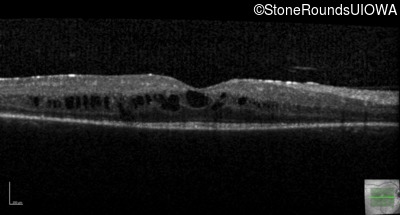

Optical Coherence Tomography - Left - 20/50 -3

Exemplar / OCT Stack